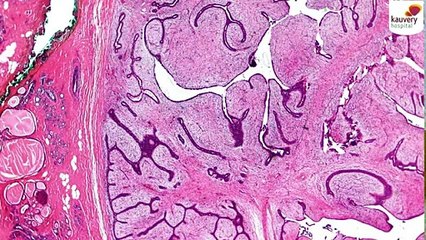

Join Dr. Raveesh Sunkara at Arete Hospitals as he breaks down the critical signs of brain tumors, emphasizes the importance of early detection, and explores the latest advancements in treatment.br br ЁЯТб What YouтАЩll Learn:br br Common symptoms to watch for.br How early diagnosis can save lives.br Cutting-edge treatment options available at Arete Hospitals.br ЁЯУ║ Click below to watch the full video and empower yourself with life-saving knowledge!br br ЁЯСЙ Watch Nowbr br ЁЯТм Have questions? Drop them in the comments, and Dr. Sunkara will address them in future videos.